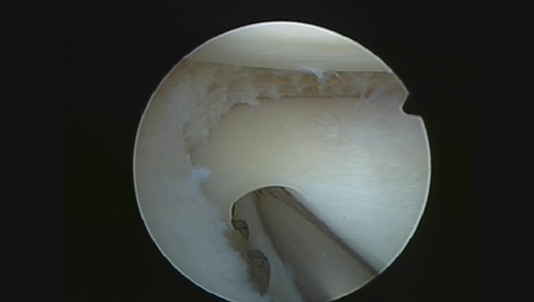

Fragment méniscal (ou « flap »)

Après régularisation

Le traitement consiste en la résection partielle du ménisque, soit sa partie instable responsable de la douleur.